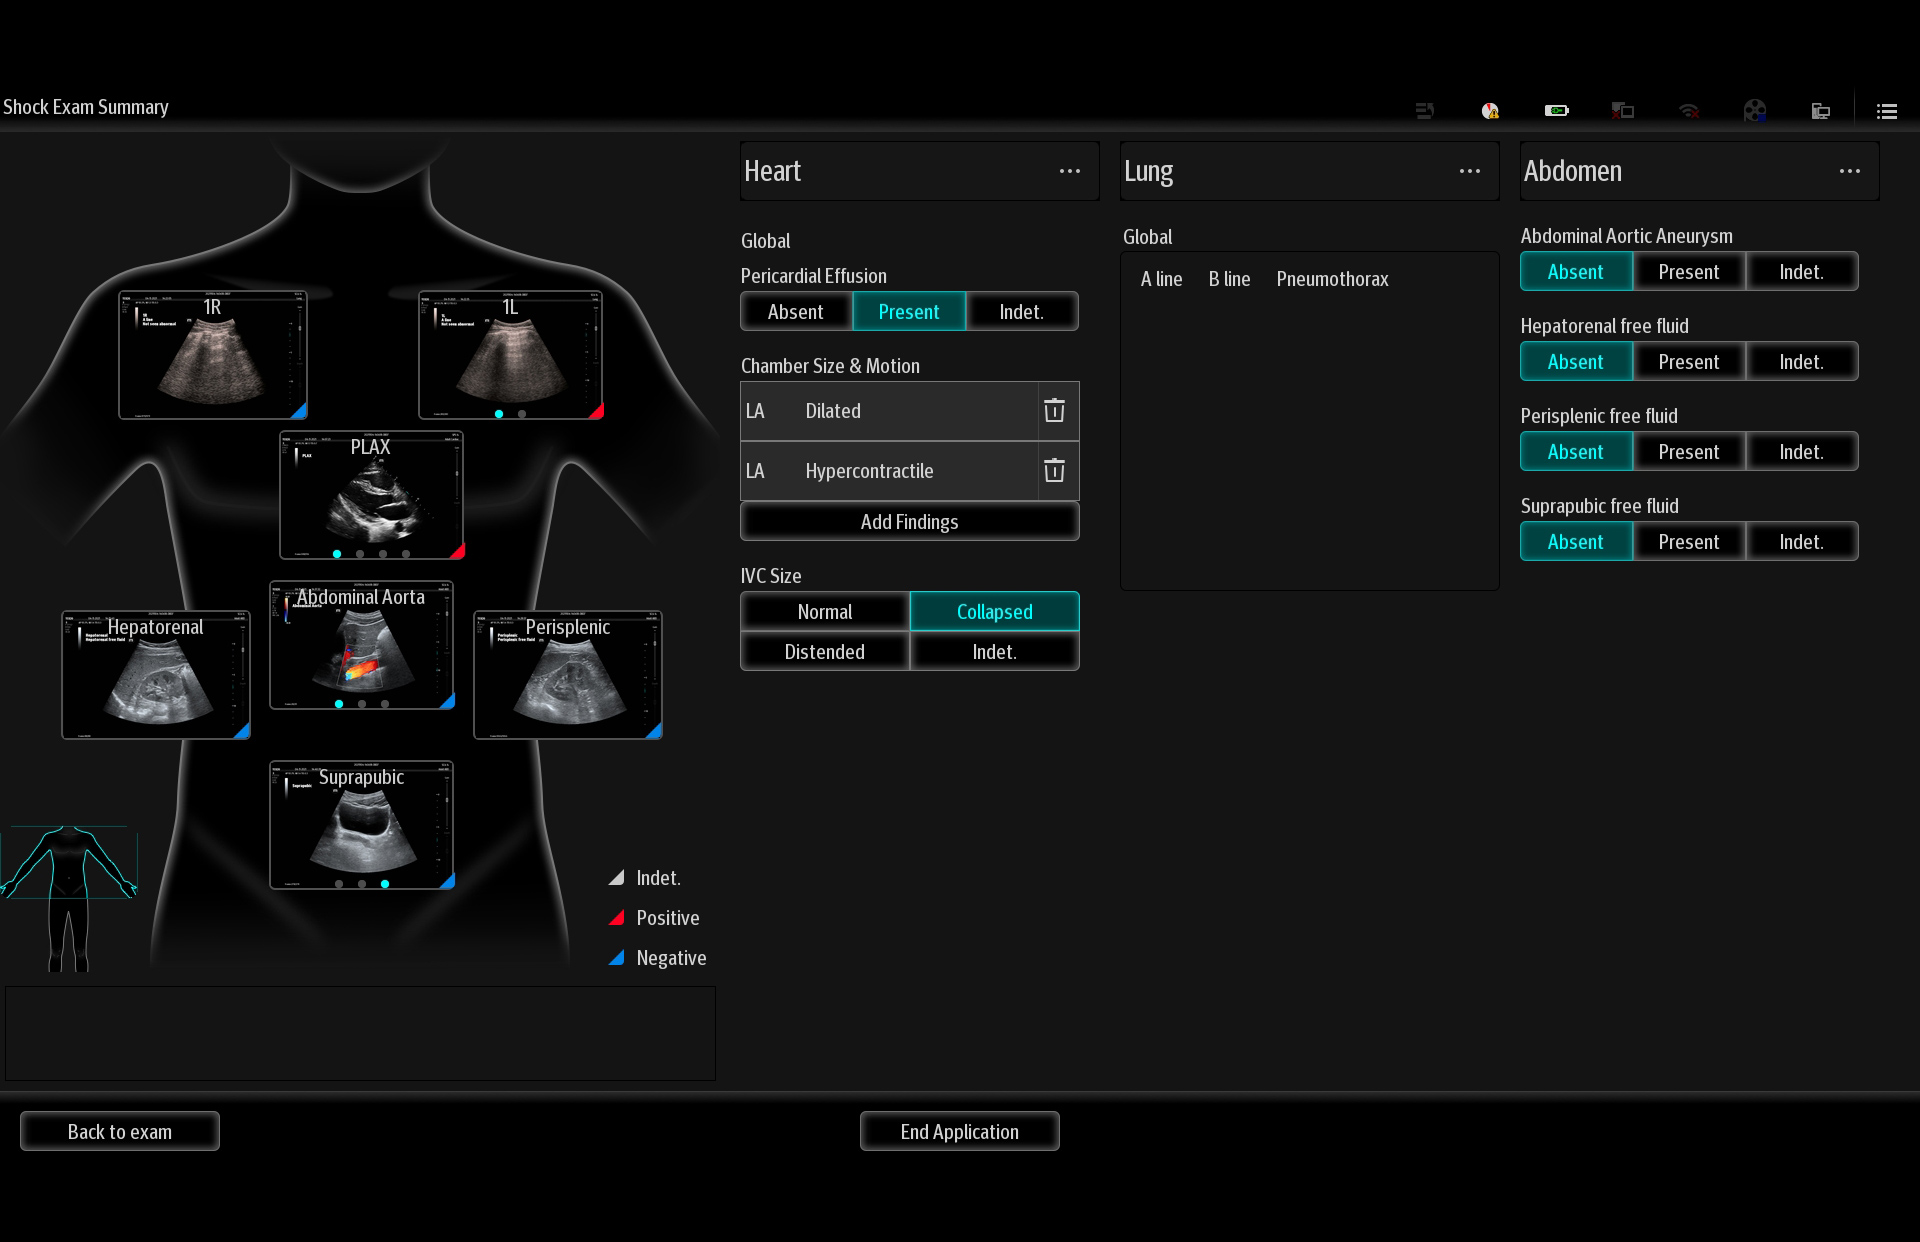

MindrayŌĆśs critical Ultrasound solutions drive improvements in care quality. Integrating advanced hemodynamic Ultrasound features, we can guarantee the highest standard of clinical care. The unique interoperability of Ultrasound and Vital sign data, we can provide comprehensive patient status data, to help inform clinical decisions, enhance clinical efficiency and, ultimately, improve patient outcomes.